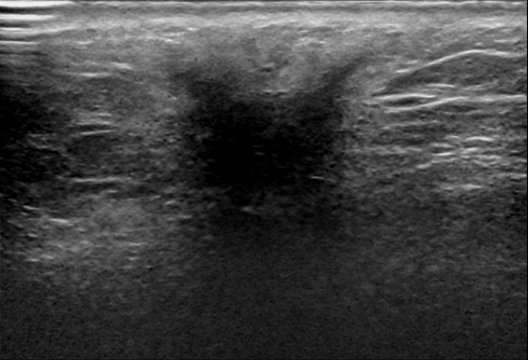

Merged Breast Dataset (MBD) The developed strategies are validated on four public breast lesion datasets, including BUSI[28], DatasetB[29], BrEaST[30], and BUS-BRA[31]. Among the datasets considered, BUS-BRA stands out for its substantial size, contributing over 1,800 images on its own. Given that all images across these datasets are meticulously annotated with pixel-level delineations, we then merged them into an enhanced dataset comprising approximately 3,000 images. We name the merged breast dataset as MBD for simplicity. We then randomly partition them into the train set, validation set, and test set in a ratio of 7:1:2. The detailed composition can be seen in Table I.

KVASIR-SEG KVASIR-SEG is an endoscopic dataset specifically created for pixel-level segmentation of colonic polyps[34], and it was featured as part of the MediaEval 2020 benchmarking challenge. The dataset includes 1,000 gastrointestinal polyp images, each paired with corresponding segmentation masks. These masks were carefully annotated and validated by board-certified gastroenterologists to ensure high diagnostic accuracy [34]. In this study, we randomly divided the dataset into 700 images for the training set, 100 images for the validation set, and 200 images for the testing set, along with their respective labels. For datasets containing validation datasets, we only validate the performance of the model during training after each epoch and iteratively save the weights that give the best performance on the validation set. When model training finishes, we reload the weights from the best-performing model for testing on the unseen test set. Otherwise, the testing set is used as the validation set instead. Some examples and corresponding labels can be seen in Figure 6.